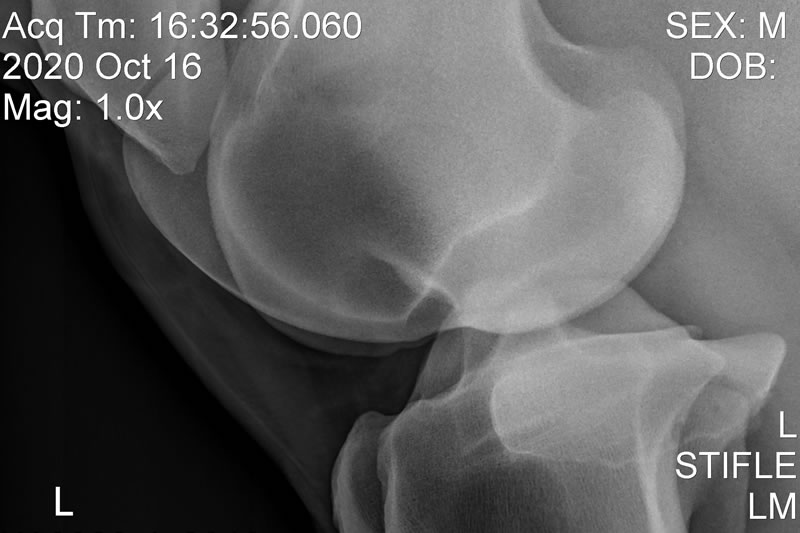

Radiology

Taking X-rays at the yard with our fully portable X-ray unit allows us to diagnose and manage limb conditions in the comfort of the stable, liaising and sharing images immediately with potential purchasers, farriers and referral centres.